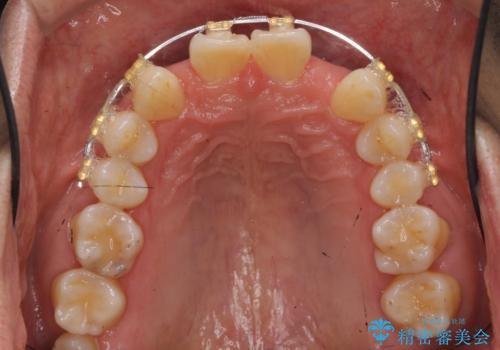

- 前歯部のすきっぱと歯並びが気になるので診て欲しいといらっしゃった方の症例です。

全顎矯正は御希望されなかったため、上顎前歯部のみの部分矯正とオールセラミッククラウンによる補綴を行いました。